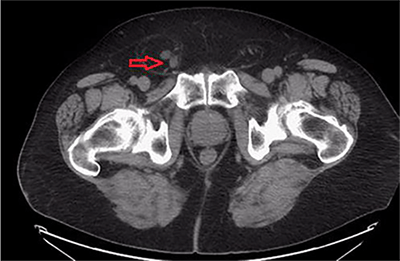

A 67-year-old male with history of hypertension, dyslipidemia, obesity, osteoarthritis, and chronic non-obstructing bilateral nephrolithiasis presented to the emergency department (ED) with a two day history of diffuse abdominal pain. He had associated polydipsia, polyuria and generalized fatigue. The patient reported the presence of chronic inguinal hernias bilaterally, which were asymptomatic and reducible for the last twenty years. During his ED evaluation he denied fever, chills, or changes in bowel habits. He did report hematuria and right sided flank pain with exertion, which he attributed to his known nephrolithiasis. The patient was afebrile and vital signs were within normal limits. Physical examination was remarkable for significant right scrotal swelling consisting of an incarcerated inguinal hernia. In addition, a reducible left inguinal hernia was present. Objective laboratory data included a complete blood cell count and liver function tests, which did not reveal any abnormalities. A renal function panel revealed an increase in the creatinine level to 1.6 mg/dL from his baseline of 0.9 mg/dL that had been constant for the past year. Given his history of nephrolithiasis with acute renal failure, the ED staff along with the medicine team decided to perform a non-contrast computed tomography (CT) to evaluate for acute urinary tract obstruction secondary to stones. The CT scan revealed the following findings: Bilateral fat-containing inguinal hernias, with the right side being larger than the left side, and interestingly, containing the right ureter, which was mildly dilated and extended into the hernia sac (Figure 1). Additionally, retroperitoneal and extraperitoneal fat extended also into the right inguinal hernia (Figure 2). The ureter distal to the sac was decompressed at the level of the internal ring, which raised the concern for incarceration of this portion of the ureter (Figure 3). Finally, the CT also revealed bilateral non-obstructing renal and bladder calculi with significant right sided hydronephrosis that was likely due to the incarcerated ureter (Figure 4).

Figure 1. Axial view of CT showing bilateral fat-containing inguinal hernias with the right side containing the ureter.